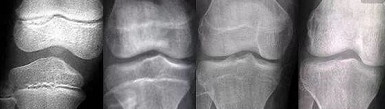

骨骼生长决定了孩子未来的高度,而骨骼闭合实际上是指长骨头两个骨骺线的消失,也就是说,它失去了自然生长的潜力。

做骨龄检测

在孩子的成长过程中,父母应该时刻注意孩子的骨龄,最好每3-5年测试一次骨龄。这是一种常用的临床方法,可以准确地显示儿童的年龄和肌肉发育。如果测量的数据差距是±3个月,属于正常发育,如果差距超过一年,需要医生干预。